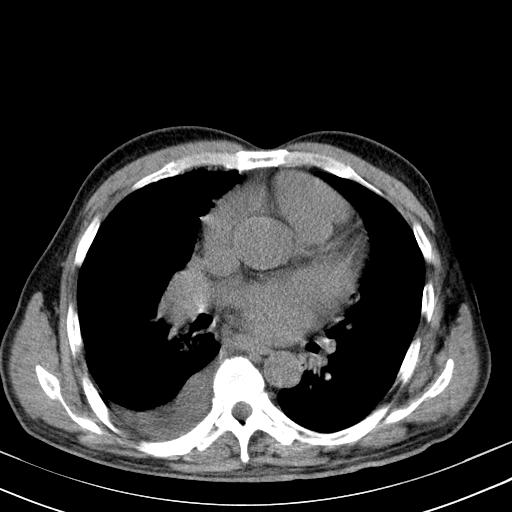

以下是引用zjzjr在2010-3-21 17:39:00的发言:[br]右下中心型肺癌并阻塞性肺炎/不张,纵膈淋巴结肿大,右侧大量胸腔积液,左侧少量胸腔积液

以下是引用zxl51642在2010-3-21 17:06:00的发言:[br]右下中心型肺癌并阻塞性肺炎/不张,纵膈淋巴结肿大,右侧大量胸腔积液,左侧少量胸腔积液,少量腹水。建议纤维支气管镜进一步检查。